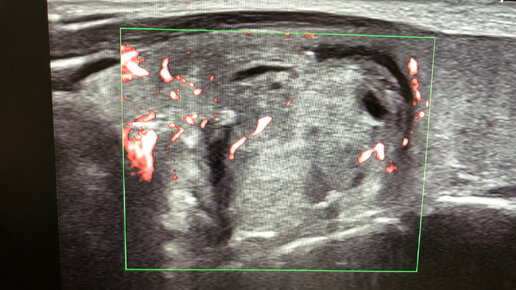

TI-RADS, «большие» и «малые» признаки злокачественности